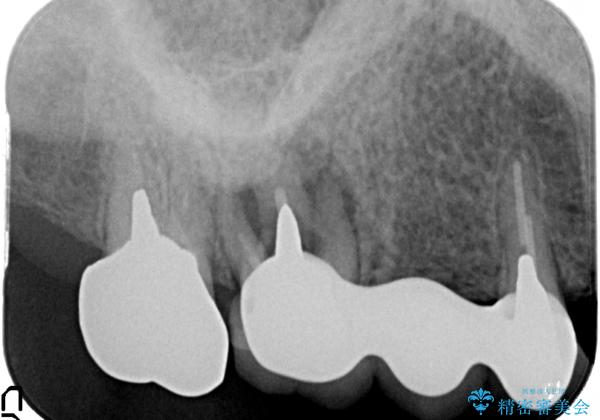

X線写真より、歯の破折(割れている状態)が認められ抜歯が必要な状態です。

隣在歯の状態から再度ブリッジ治療は勧められず義歯(入れ歯)かインプラントのうち、よりしっかりと噛めるようになるインプラント治療を希望されました。